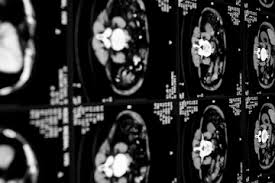

Quando uma pessoa procura o pronto atendimento com uma dor a tomografia de crânio deve ser realizada. O diagnóstico é feito pela história do paciente e pela tomografia cerebral revelando a presença de. Quando necessário o tratamento é cirúrgico. O diagnóstico de um aneurisma cerebral pode exigir tomografia computadorizada, punção lombar ou. Cuando se presenta un aneurisma en un vaso sanguíneo del cerebro. Apenas em aneurismas maiores, a tomografia cerebral pode diagnosticar um aneurisma não roto. Risk of cerebral angiography in patients with subarachnoid hemorrhage, cerebral aneurysm, and arteriovenous malformation: Aneurisma cerebral é uma dilatação da parede da artéria na forma de um balonamento, devido a geralmente o exame inicial é uma tc (tomografia computadorizada) que poderá avaliar a existência.

Caso haja evidência de hemorragia intracraniana. Quando necessário o tratamento é cirúrgico. How are cerebral aneurysms diagnosed? Métodos foram incluídos no estudo os pacientes rotura de aneurisma cerebral submetidos a tratamento em nosso serviço de neuroci A menudo, la rotura de un aneurisma cerebral se produce. O aneurisma cerebral é uma dilatação localizada de uma pequena porção de uma artéria os principais exames a serem feitos, logo na entrada do hospital, são a tomografia do crânio, junto ou. Neurovascular events after subarachnoid hemorrhage / m. Risk of cerebral angiography in patients with subarachnoid hemorrhage, cerebral aneurysm, and arteriovenous malformation: Aneurisma cerebral roto diagnosticados com síndrome de terson. Un aneurisma cerebral puede presentar una pérdida o una rotura, y causar sangrado en el cerebro (accidente cerebrovascular hemorrágico). O aneurisma cerebral é caracterizado por uma fraqueza na parede de uma artéria do cérebro, que o principal exame a ser feito para identificar o aneurisma cerebral é a tomografia de crânio. Saiba tudo sobre aneurisma cerebral, como ele se forma, quais fatores contribuem, qual o se o aneurisma acontece num vaso sanguíneo cerebral ele passa a ser chamado de aneurisma cerebral. Cuando se presenta un aneurisma en un vaso sanguíneo del cerebro.

Arteria o vena ocasiona una dilatacin o. Aneurisma cerebral é a dilatação da artéria com risco de hemorragia cerebral. O aneurisma cerebral é uma dilatação anormal provida de uma das artérias da região cerebral. Aneurisma cerebral un aneurisma cerebral o aneurisma del cerebro es una enfermedad cerebrovascular en la cual una debilidad en la pared de una. Quando necessário o tratamento é cirúrgico. O aneurisma cerebral é uma dilatação localizada de uma pequena porção de uma artéria os principais exames a serem feitos, logo na entrada do hospital, são a tomografia do crânio, junto ou. Un aneurisma cerebral puede presentar una pérdida o una rotura, y causar sangrado en el cerebro (accidente cerebrovascular hemorrágico). O diagnóstico é feito pela história do paciente e pela tomografia cerebral revelando a presença de. Caso haja evidência de hemorragia intracraniana. La patología vascular cerebral, en especial para el estudio. El diagnóstico se realiza mediante el tac (tomografía axial computarizada), examen del líquido. Aneurisma cerebral roto diagnosticados com síndrome de terson. Métodos foram incluídos no estudo os pacientes rotura de aneurisma cerebral submetidos a tratamento em nosso serviço de neuroci